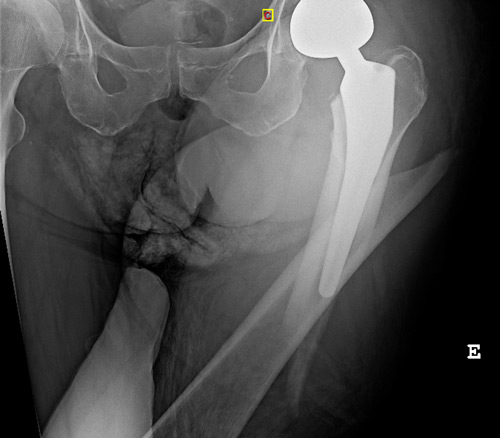

Imagery

What classification allows us to classify this fracture and what is its grade?

• ✔️Vancouver classification grade B1

The French Society of Orthopedic Surgery and Traumatology (SoFCOT) recommended a specific Remaining Attachment Index (RAI) to asses residual fixation. Remaining Attachment Index < 2/3 in Vancouver B1 periprosthetic hip fracture is a risk factor for early implant loosening after isolated internal fixation

Remaining Attachment Index (RAI)